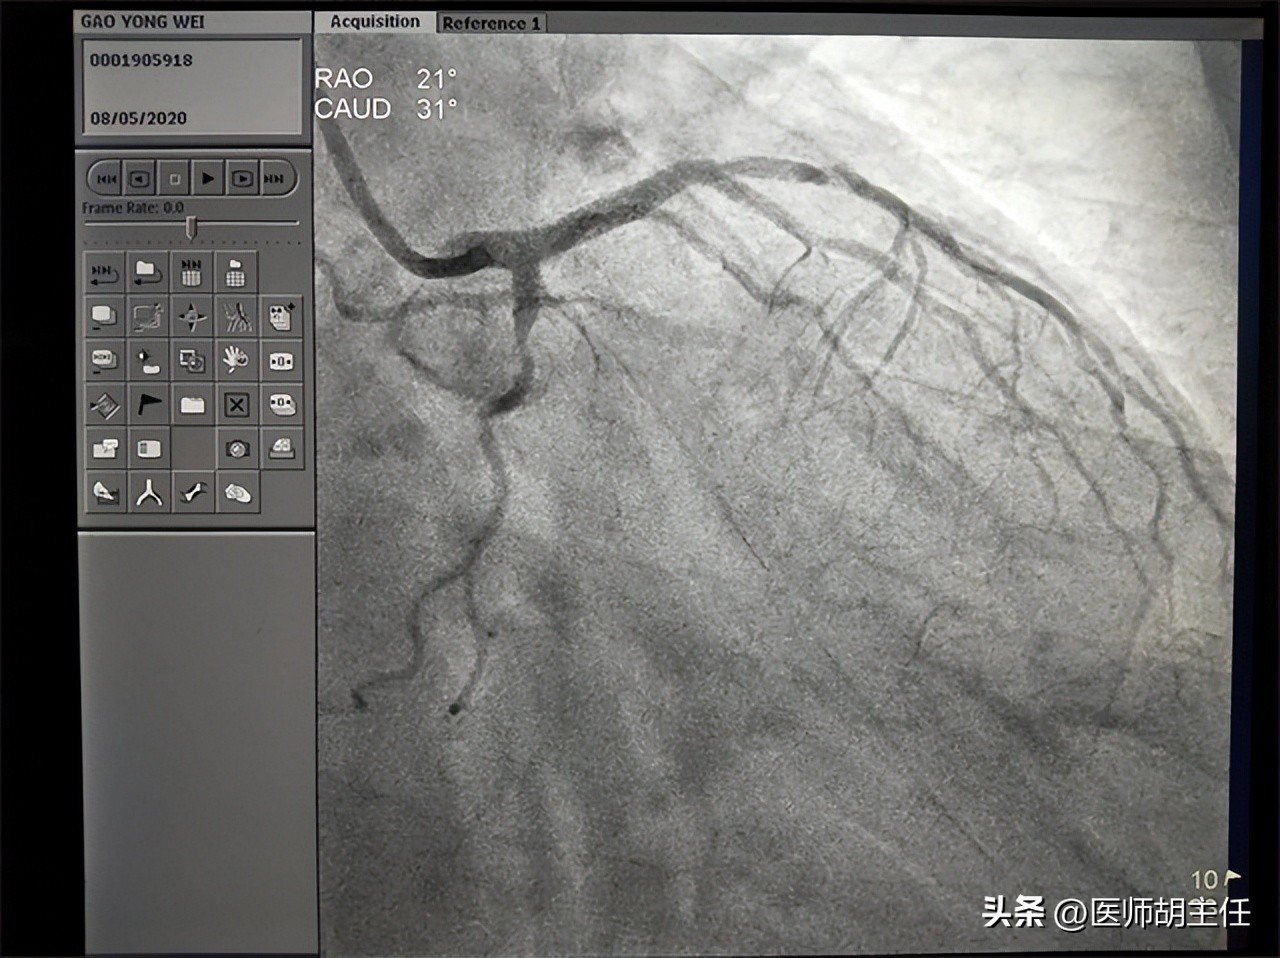

冠脉造影是一种有创的冠脉介入性检查方法。是临床用于诊断冠状动脉粥样硬化性心脏病的“金标准”。

冠状动脉的主要操作方法为,用特殊的导管找到下肢股动脉或者上肢桡动脉然后刺入,再沿着主动脉上行找到冠状动脉,将造影剂注入就会使左右冠脉在X光下显影,这样就可以判断冠状动脉有无斑块、狭窄、堵塞以及堵塞的面积,以此来确定病灶以及手术方案(支架或者搭桥等),支架手术多是在造影的同时进行,在造影的整个过程中患者保持平躺的体位,造影的创口非常小,仅为一个小出血点,按压便能止血。